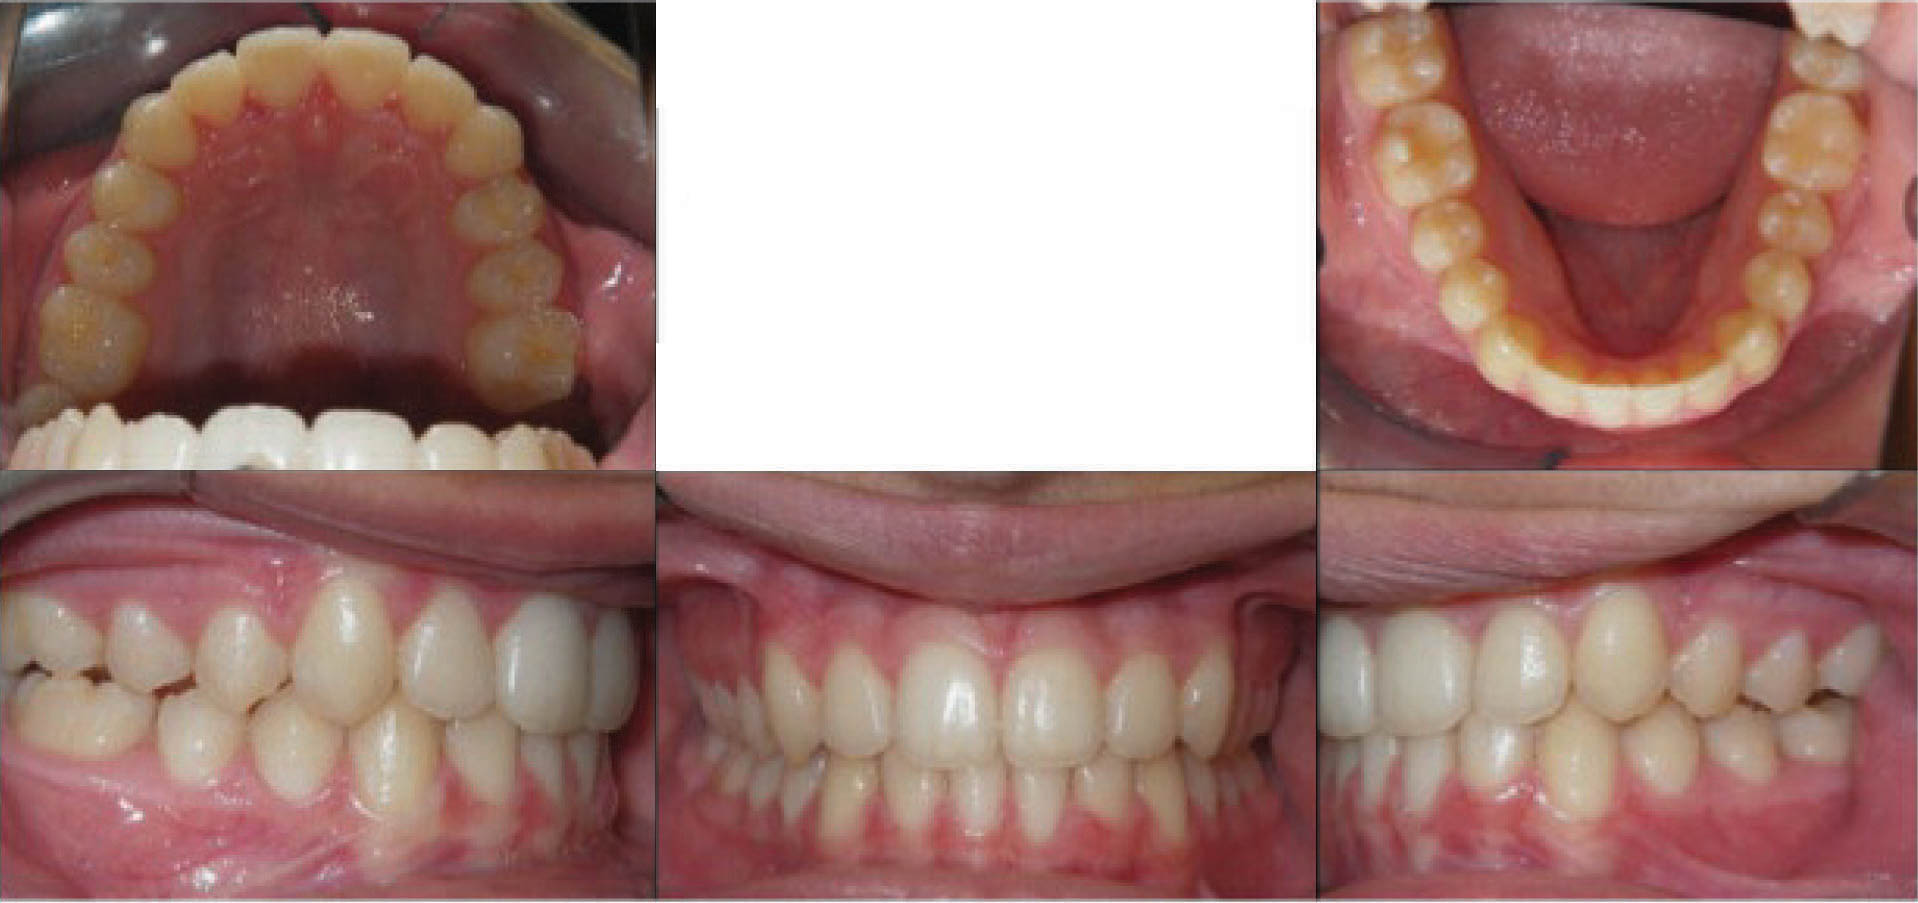

بیمار بعدی یک دختر ۱۶ ساله ClII/1 با اوربایت نرمال و اورجت زیاد است. کرادینگ مختصر دو فک دارد، قوس بالا تنگ، و پروفایل او طبیعی است (شکل 83-۶ الی 85-۶). در این بیمار از الاستیک کلاسII استفاده شده است. الگو اسکلتی طبیعی، رادیوگرافی لترال سفالومتری نشان دهنده دندانهای قدامی پروترود شده بالا با الگو طبیعی اسکلتی میباشد. رادیوگرافی OPG طبیعی است. قسمت بعُد افقی چک لیست را به این نحوه پر کردیم:

شکل 83-6

شکل 84-6

شکل 85-6

از الاستیک کلاسII برای اصلاح رابطه افقی استفاده گردیده است. شروع الاستیک کلاسII بعد از مرتب شدن دندانها بود و از الاستیک ۴ انسی استفاده نمودیم چون میزان اصلاح زیاد بود.